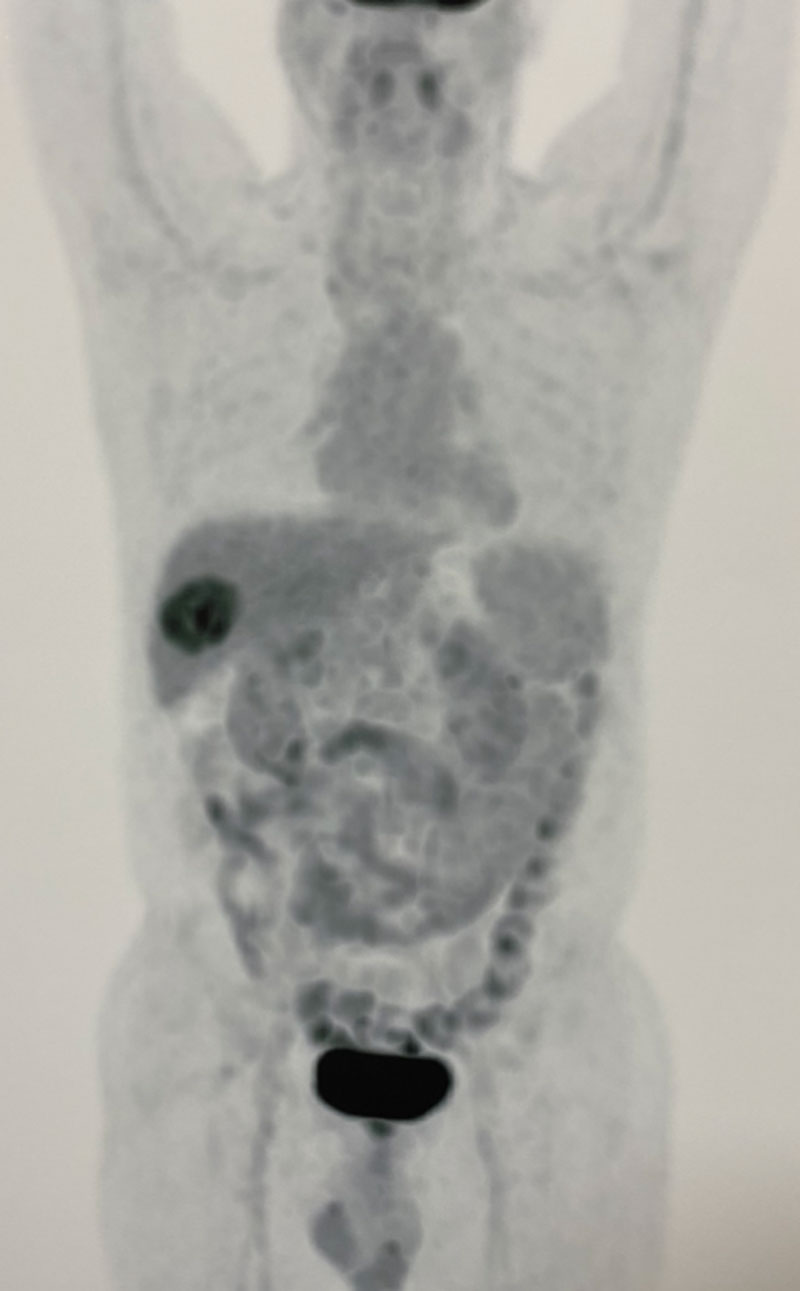

63 year old gentleman presented with right upper abdominal pain, loss of appetite, loss of weight & a USG report showing a gall bladder mass involving liver. Patient was thoroughly investigated. Investigations (PET-CT scan,MRI & tumor marker CA19-9 were highly in favour of a gall bladder cancer which could be completely removed. Hence immediate surgery was conducted without any preoperative biopsy to avoid any tumor spillage. An intraoperative controlled biopsy (Frozen section) confirmed the malignancy. The tumor was removed in toto along with portion of attached liver and draining lymph nodes. Patient recovered well in 5 days and was discharged. He was recommended postoperative chemotherapy based on the histopathology (adjuvant chemotherapy) A chemoport was inserted for the ease of delivering chemotherapy in a safe and painless manner. Patient was put on a strict follow up protocol.

1. It is vital that patient is properly investigated using PET-CT scan, MRI, Liver function tests & tumor marker CA19-9.